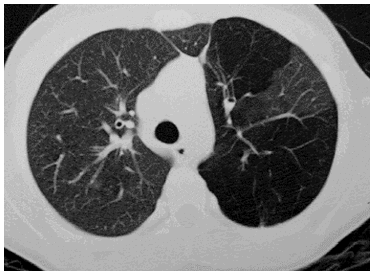

Es una lesión redondeada, de pared fina y bien definida, por lesión en el parénquima y que tiene contenido aéreo o líquido:

Quiste

Si se rompe el neumatocele puede ocasionar:

Neumotórax

¿Cuáles son dos presentaciones que pueden tener los quistes?